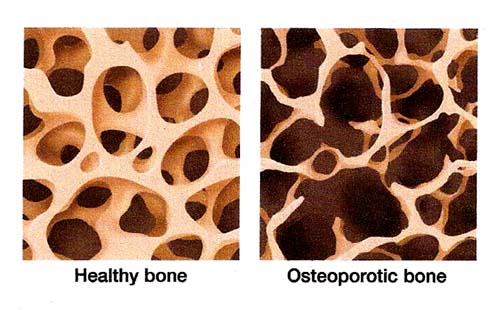

Galinhas poedeiras também podem ser acometidas por distúrbios locomotores. Devido à alta demanda de cálcio para a produção de ovos, estas categorias são frequentemente afetadas pela fragilidade óssea, sendo comum a ocorrência de osteoporose – um tipo de desordem metabólica. A osteoporose pode ser observada, de maneira geral, em todas as galinhas poedeiras – mesmo quando há um adequado fornecimento mineral. Contudo, a severidade da osteoporose nesta categoria é muito variada (Thorp, 1994).

Além das perdas produtivas observadas pela incidência de problemas locomotores nos sistemas produtivos da avicultura industrial, é possível observar que estes distúrbios acarretam em uma redução significativa do bem-estar animal. Em comparação aves selvagens, os frangos de corte e poedeiras tendem a caminhar menos em busca do alimento. Devido a alta densidade de alojamento destes animais em sistemas de produção, muitas vezes a identificação de problemas locomotores torna-se uma tarefa difícil. Contudo, o entendimento das causas destes problemas – como o manejo do ambiente proporcionando melhores condições da cama ou de higiene, pode contribuir para a redução de problemas locomotores. Um correto manejo nutricional de galinhas poedeiras, ajustando o fornecimento de cálcio e a relação cálcio:fósforo da dieta também são alternativas para se reduzir a incidência de osteoporose. Dessa forma é possível contribuir para o bem-estar dos animais nestes sistemas e reduzir perdas por condenações de carcaça ou desclassificações na linha de abate.